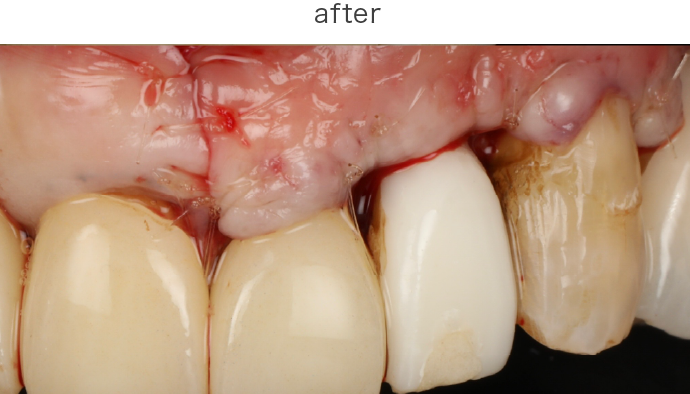

SRPでも改善が見られない重度の症例では、歯肉を切開してポケット奥深くまで歯石などを除去する外科的処置を行います。

歯周病によって破壊された歯周組織(歯肉・歯槽骨など)を、骨補填材や薬剤を用いて再生を促す治療です。適応症例・術後管理が重要です。

| 治療内容 | 下段 歯周外科(再生療法) |

| 治療費 | 総額 88000円〜 |

| 治療回数 | 1回 |

| リスク | 術部の発赤、腫脹、疼痛、部分的なネクローシス |